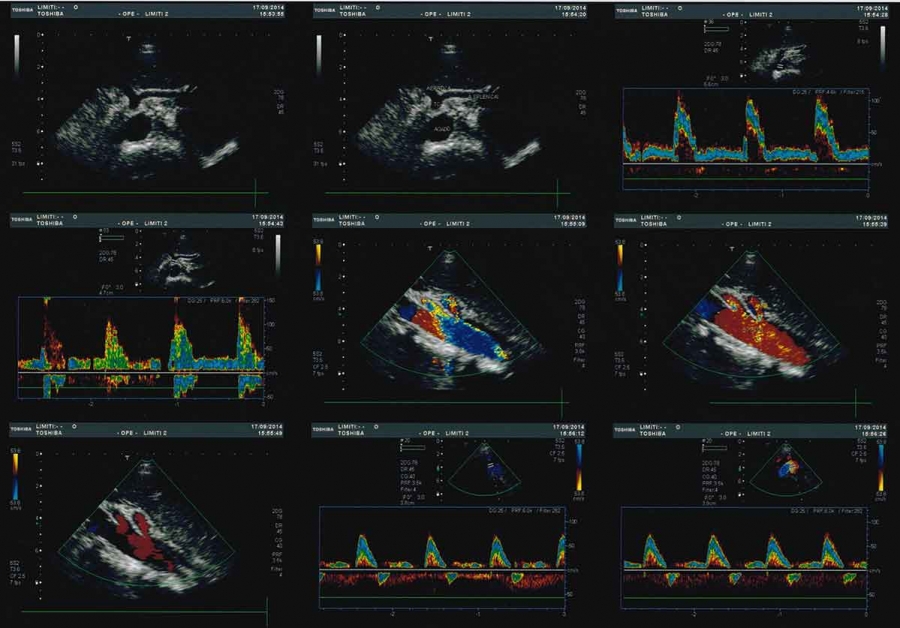

Ecocolordoppler dell’aorta addominale

L’esame ecografico dell’aorta addominale ha principalmente lo scopo di identificare per tempo la dilatazione ( aneurisma ) di questa grossa arteria. L’esame consiste nell’appoggiare una sonda ecografica sull’addome, da sotto lo sterno fino all’ombelico, e nella registrazione delle immagini e dei grafici doppler.

L’esame semplice e privo di radiazioni serve pertanto ad individuare tale patologia, seguirla nel tempo e, quando necessario, porre l’indicazione ad un intervento chirurgico ( aneurismectomia ). Con la metodica in oggetto, in casi selezionati, si può anche verificare la possibilità di un’intervento mediante applicazione di endoprotesi.